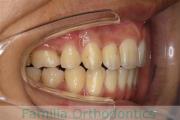

歯並びを治したいということで来院されました。下あごがやや右側に偏位して後退している、上顎前突(出っ歯)でした。上下左右から小臼歯を抜歯して、歯科矯正用アンカースクリューを併用したマルチブラケット法にて治療を行いました。約2年、24回の来院をしていただきました。

下顎の後退はいびきなどの上部気道の障害が出やすいと考えられます。